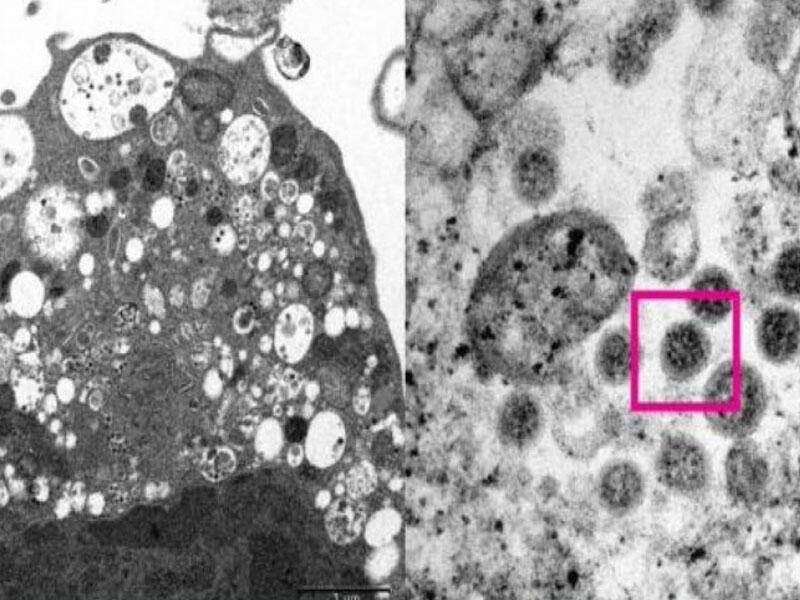

Milli.Az lent.az-a istinadla bildirir ki, BioRxiv-də paylaşılan tədqiqat nəticələri göstərib ki, virusun Alpha, Beta, Delta və Omicron variantları plastik səthlərdə və dəridə Wuhan ştammından 2 dəfə çox yaşaya bilir. Tədqiqatda Vuhan tipinin plastik səthlərdə orta ömrü 56 saat, Alpha variantının 191,3 saat, Beta variantının 156,6 saat, Delta variantının 114 saat, Omicron variantının isə 193,5 saat, İnsan dərisində isə virusun dəyişməmiş halının 8,6 saat, Alpha variantının 19,6, Beta variantının19,6, Delta variantının 16,8 və Omicron variantının isə 21,1 saat canlılığını qoruduğu nəticəsini əldə ediblər. Tədqiqatçılar həmçinin qeyd ediblər ki, virusun bütün variantları 35 faiz spirt məhlulu ilə təmasda 15 saniyə ərzində təsirini itirirlər.